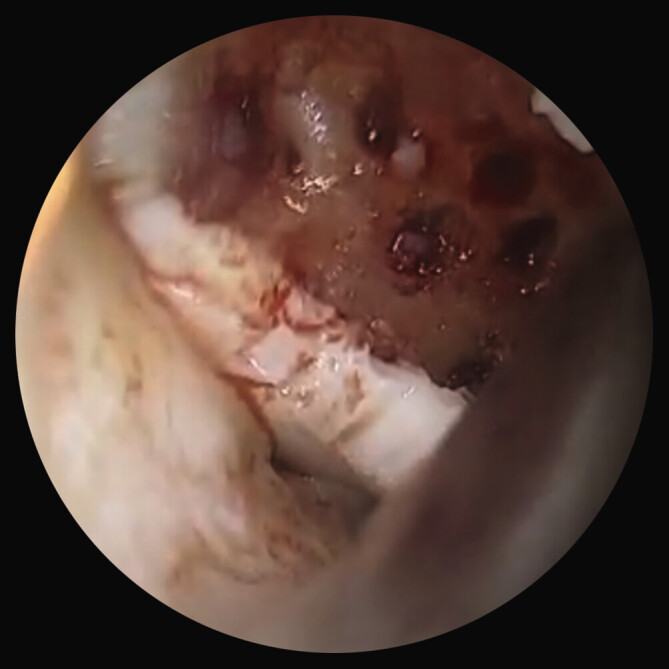

Methods: We describe a case of a patient suffering from OD with a bone lesion in the weight-bearing area of medial femoral condyle. Arthroscopy was performed and an osteochondral fragment from the medial femoral condyle was observed and two articular loose bodies were removed. After months, the patient returned with pain and a locked knee. magnetic resonance imaging (MRI) presented a new unstable chondral flap at the posterior border of the previous lesion. Surgery was performed again, and at open examination, the previous OD lesions were covered by regenerative tissue, with a lesion of 3 cm2 at the inferior medial part of the chondral flap. The peripheral margins were cleaned, and a subchondral crater was curetted. The subchondral lesion was debrided, and the flap was fixed with pins and a central bioresorbable screws.